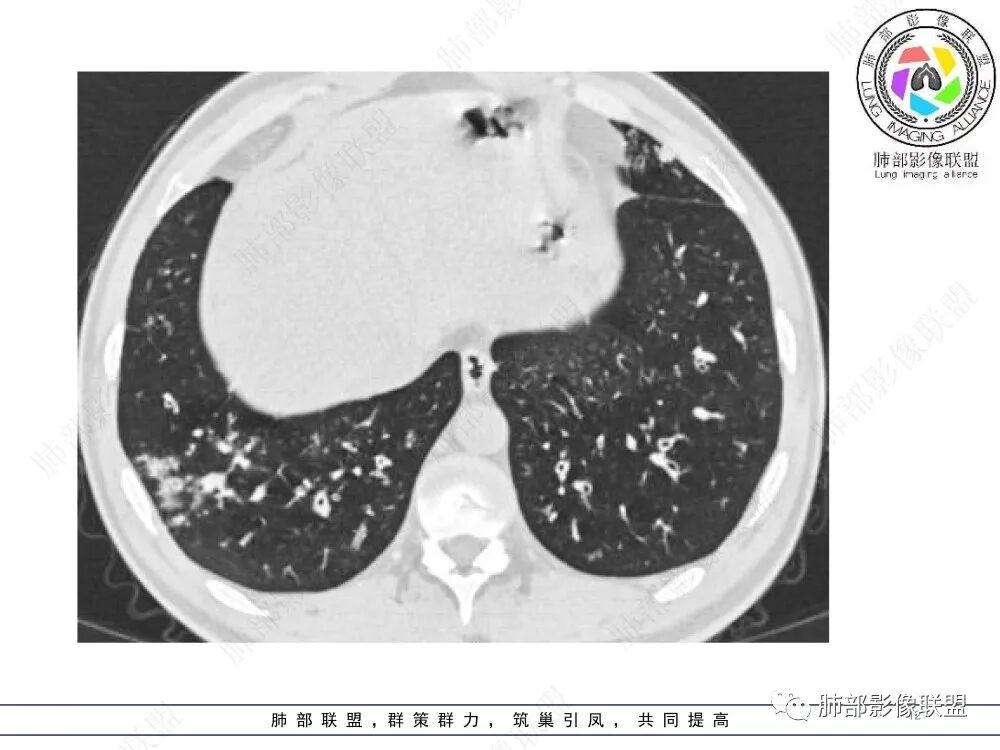

中年男性,慢性咳嗽,有吸烟史,胸部CT基础尚可,双肺多发的沿支气管播散的树芽影以及支气管管壁的增厚和对应区域内的斑片影实变影,符合气道播散的表现。经过对症抗感染治疗1月之后,胸部CT影像进展。右侧播散到左侧。实变和漱牙以及气管壁增厚均较前明显进展。

35岁男性,慢性咳嗽2月余,吸烟17年。弥漫支气管壁增厚,腔部分增宽,部分狭窄,远端粘液栓,树芽征,边界模糊,抗炎无效。

6/13复查,外围出现斑片状实变影,周围GGO,从发病过程:支气管壁增厚,延续到小气道炎症,然后周围实变,首先气道来源病变,因为支气管壁的增厚,腔狭窄、扩张,其次病变广泛,几乎累及所有叶段,常规思路:气道侵袭性曲霉菌病;不除外努卡。与NTM鉴别,NTM其实支气管扩张为中型的多为中外带支气管扩张,中近端支气管改变不明显,这个中内带明显,而且早期是中内带为主。

2.胸部CT:两肺广泛的支扩,支气管壁增厚,多发的树芽影,部分伴有支气管周围的渗出,少量实变。不足一月复查,原有支扩、支气管壁增厚基础上伴有大量渗出,实变,结节,胸膜下累及。